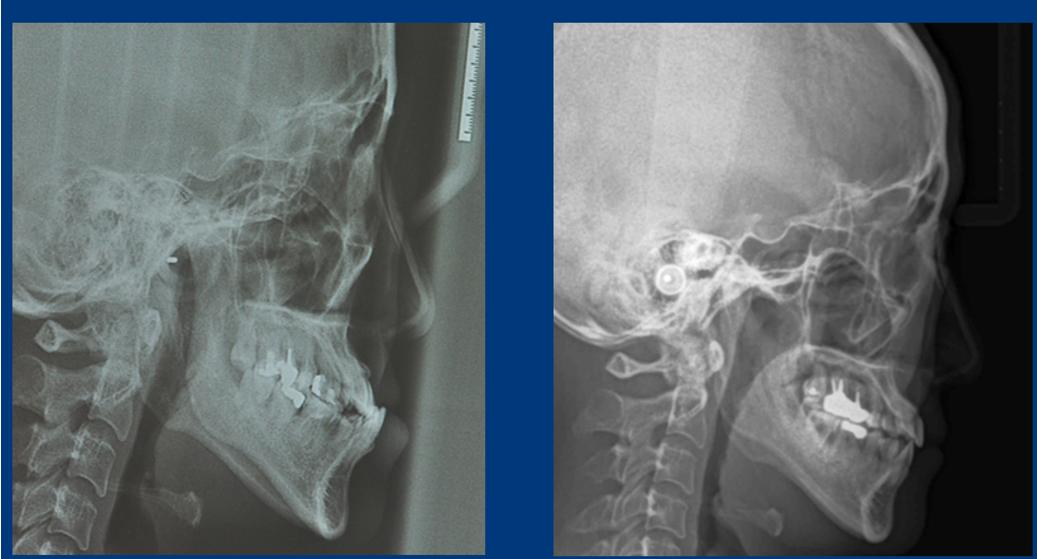

这是矫正结束一年之后的复查,咬合关系正常,未出现反弹,x线对比: